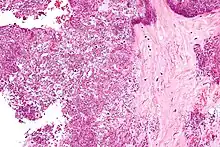

Arthrocentesis, or removing synovial fluid from the affected joint, is performed to test the synovial fluid for the calcium pyrophosphate crystals that are present in CPPD. When stained with H&E stain, calcium pyrophosphate crystals appears deeply blue ("basophilic").[10][11] However, CPP crystals are much better known for their rhomboid shape and weak positive birefringence on polarized light microscopy, and this method remains the most reliable method of identifying the crystals under the microscope.[12] However, even this method has poor sensitivity, specificity, and inter-operator agreement.[12]